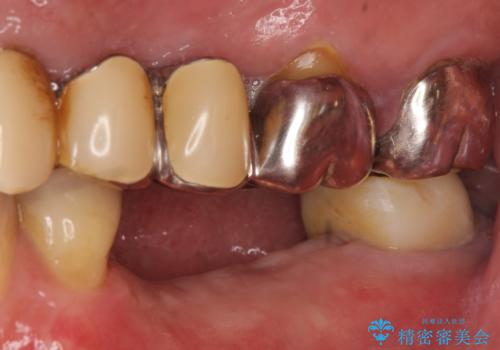

欠損部位である左下5、6番目にインプラントを埋入し、オールセラミッククラウンによる補綴を行いました。

左下7番目は再根管治療を行い、オールセラミッククラウンによる補綴を行いました。

オールセラミッククラウンについて

今回用いたオールセラミッククラウンはジルコニアフレームという白い素材の上にセラミックを盛っているため、審美性が非常に高いのが特徴です。

また、ジルコニアは人工ダイヤモンドの材料にも使われているほど高い強度を持っており、そのためオールセラミッククラウンは審美性だけでなく、奥歯やブリッジの補綴も可能とするクラウンです。